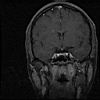

Schedel